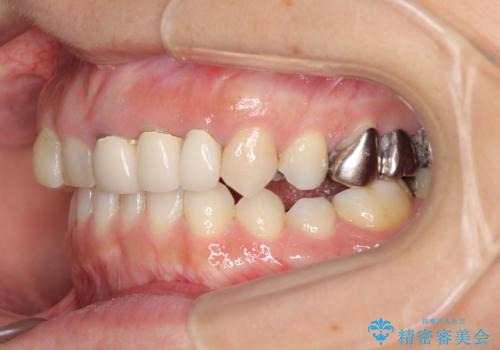

診察したところ、上顎前歯に過剰歯があることで上顎歯列が大きくなり、上下の歯が奥歯の一部でしか咬み合っていない状態でした。

そのため右下の奥歯に強い負担が生じていて、むし歯が大きかったこともあり、抜歯が必要な状態でした。

咬み合わせ改善のため、前歯の過剰歯を抜去し、ワイヤー矯正にて歯列と咬み合わせることとしました。

左上の奥歯のブリッジや前歯のセラミッククラウンはいったん除去し、矯正治療後に補綴治療を行うこととしました。

また、右下の抜歯が必要な奥歯は、矯正治療の途中でインプラントを埋入し、矯正治療後に上顎と合わせて補綴治療を行うこととしました。